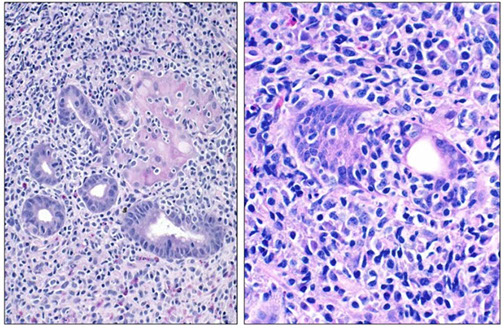

Cutaneous lymphoid hyperplasia in a 72-year-old man who presented with several purple-brown plaques on his cheeks and temples. A, The nodular infiltrate extends through the dermis with sparring of the overlying epidermis. B, It is characterized by scattered follicles with well-defined, reactive-appearing germinal centers, some of which have surrounding mantle zones. Many CD20-positive B cells are in the reactive follicles (C), and more numerous CD3-positive small T cells are present in the interfollicular areas (D). B-cell clonality studies (not shown) were negative for a clonal IGH or IGK gene rearrangement. [19]